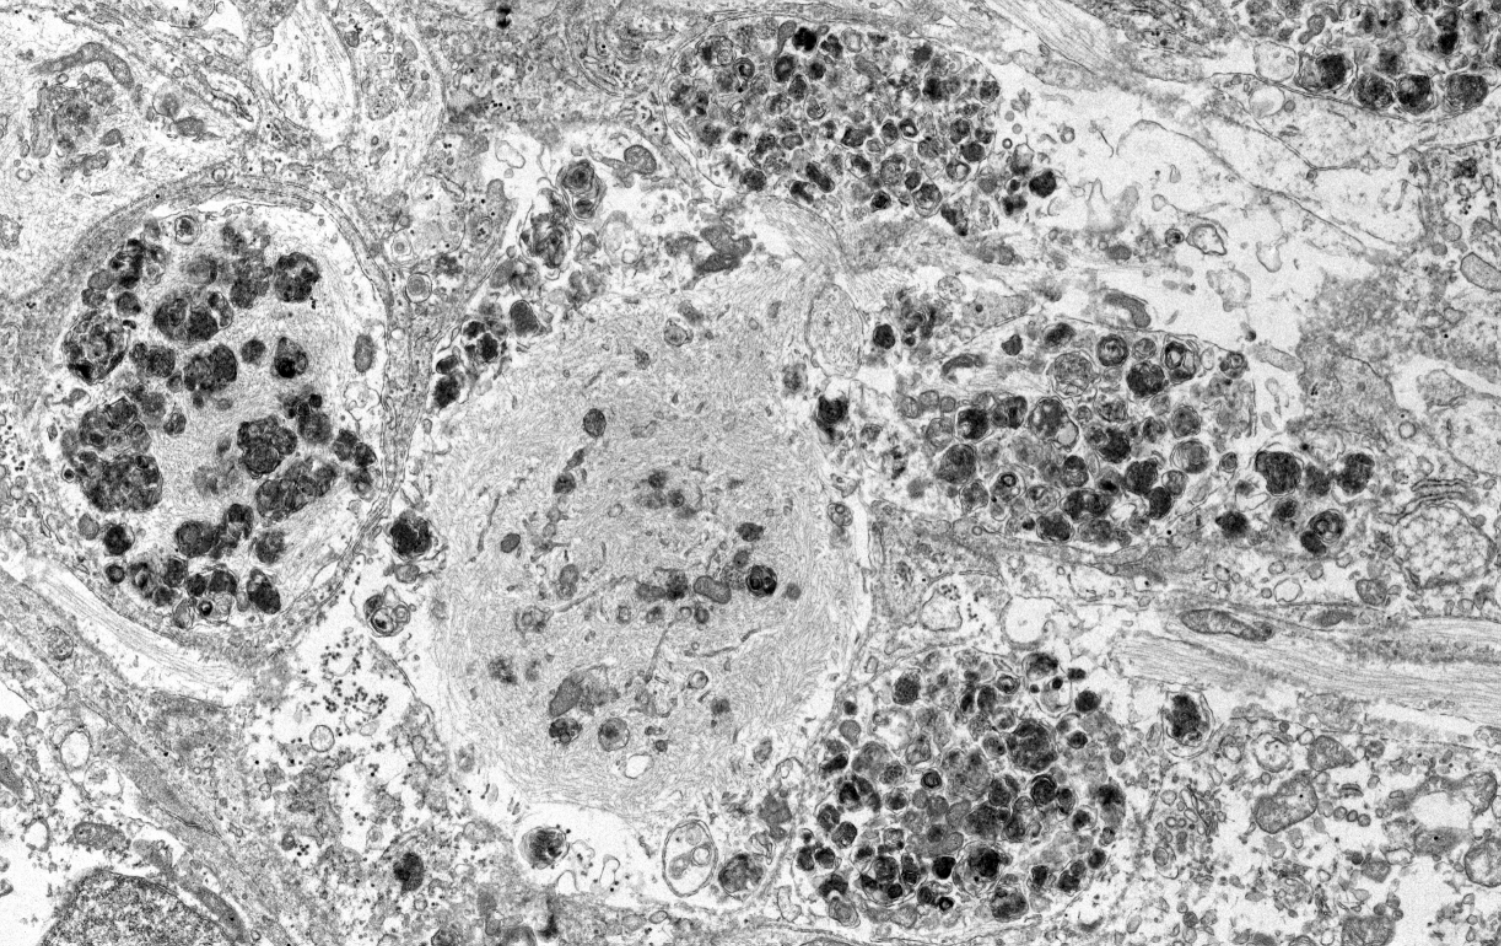

I developed a dual-hit model of Parkinson's disease in iPSC-derived dopaminergic neurons, published as a first-author paper in Nature Neuroscience (2024). Sequential exposure to α-synuclein preformed fibrils (PFFs) followed by proinflammatory cytokines (IFN-γ) drives formation of Lewy body–like inclusions — 5–10 µm membrane-bound perinuclear structures containing fibrils, damaged lysosomes, mitochondria, and filamentous material. These inclusions form in 15–20% of DA neurons over 14 days, are ThS-positive (amyloid-containing), and are phospho-α-synuclein–enriched — closely resembling patient-tissue Lewy bodies by EM.

PFFs bypass early endosomes and reach LAMP1⁺ lysosomes within 2 min. Nanogold EM tracing confirms rapid transit. Fibrils resist degradation and accumulate, causing lysosomal dysfunction.

Dual-hit pathological cascade: Activated microglia release proinflammatory cytokines (IFN-γ, TNF, IL-1β) that compromise lysosomal function in DA neurons. Exogenous α-synuclein PFFs enter via macropinocytosis, accumulate in dysfunctional lysosomes, seed endogenous α-synuclein, and drive formation of 5–10 µm membrane-bound Lewy body–like inclusions containing fibrils, damaged mitochondria, and disrupted organelles. From Bayati et al., Nature Neuroscience 2024.